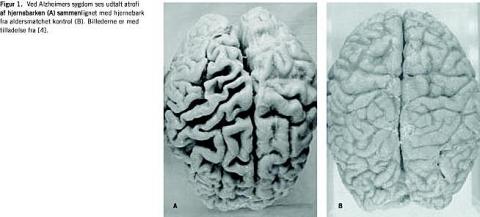

Patoanatomisk er hjernen fra patienter med Alzheimers sygdom karakteriseret ved udtalt atrofi, som i den tidlig fase af sygdommen især rammer de centre i hjernen, som berører hukommelses- og indlæringsprocesserne (Figur 1). I frontal- og temporallapperne ses der således en væsentlig atrofi, som skyldes degenerering af neuritter og synapser i såvel det kolinerge som det glutamaterge system. De AD-specifikke hjernelæsioner udgøres af ekstracellulære proteinaflejringer (senile plaques) og intracellulære fibriller (neurofibrillary tangles), som tidligt i forløbet især findes ophobet i hippocampus, det entorinale cortex og amygdala. Kombinationen af disse forandringer, som blev beskrevet af Alois Alzheimer i 1907 [5], er patognonomisk for AD.